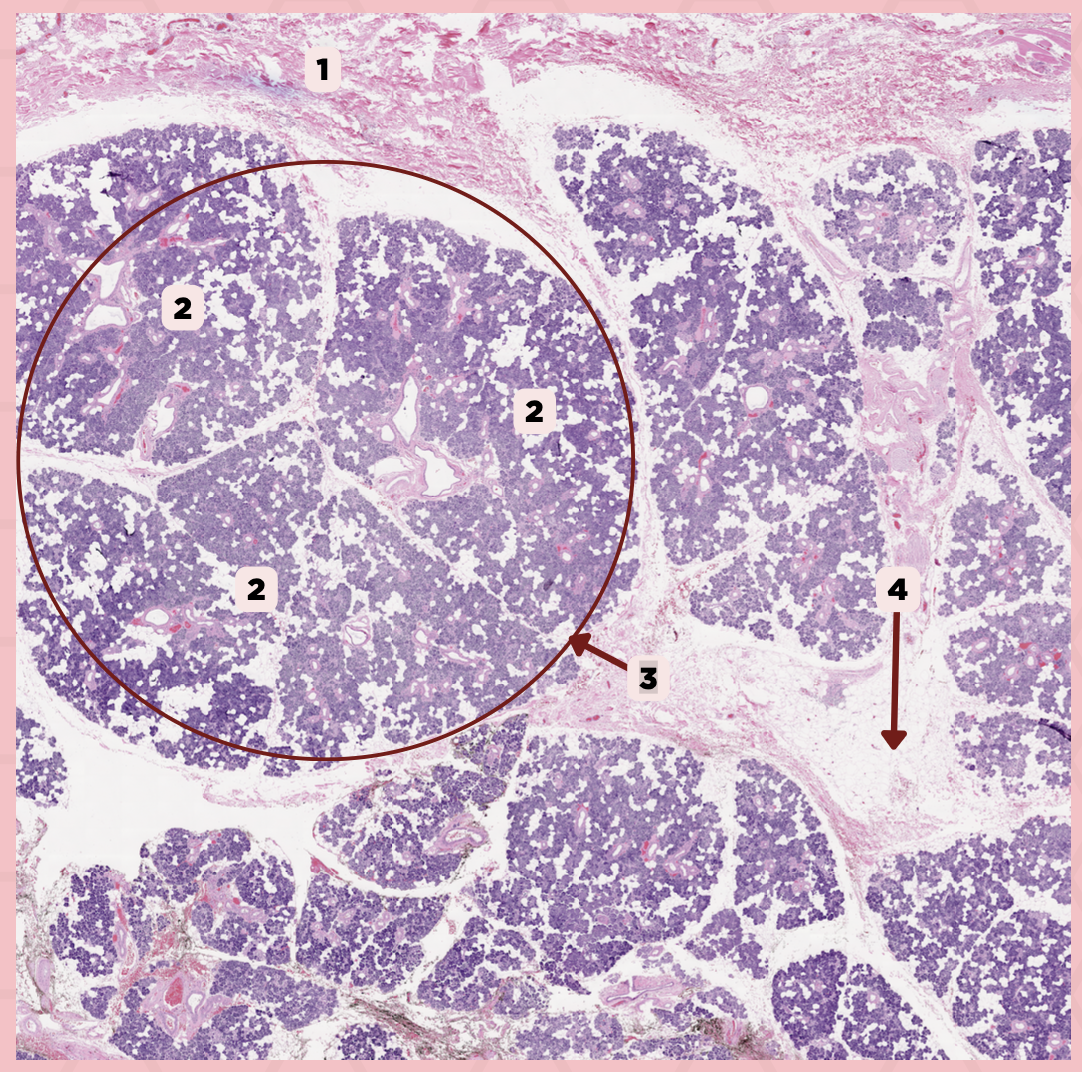

Parotid

Identify the specimen.

Capsule

Identify the structure labeled as 1.

Septa

Identify the structure labeled as 2.

Lobule

Identify the structure labeled as 3.

Lymph Node

Identify the structure labeled as 4.